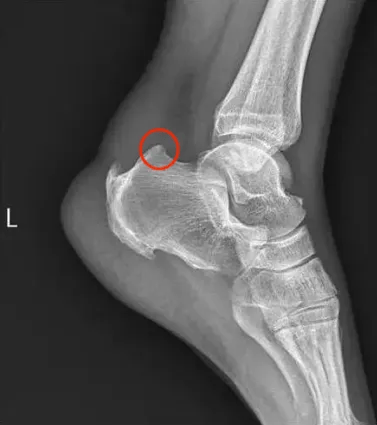

5.跟骨夹角(Fowler-Philip Angle)测量:即水平面与跟骨后缘的夹角(Flower-Philipp angle)>75°,正常角度一般不超过69°;

5.X线侧位片评估骨突程度。